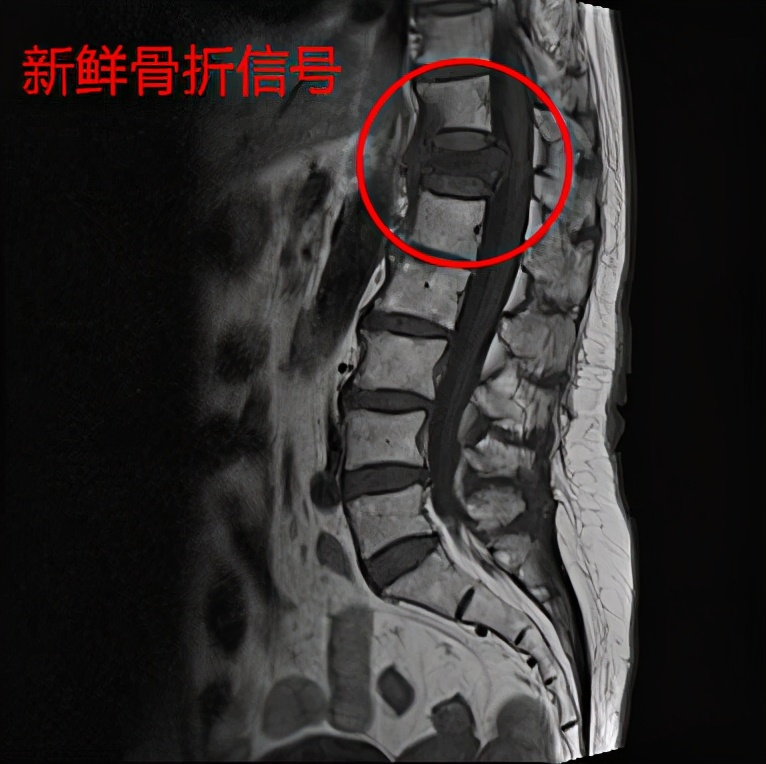

而核磁共振可以明确是否是新发生(新鲜)的骨折,因为陈旧的压缩性骨折在X线片上也是压缩性改变。

翻身疼深呼吸疼是怎么回事,向左翻身疼是怎么回事